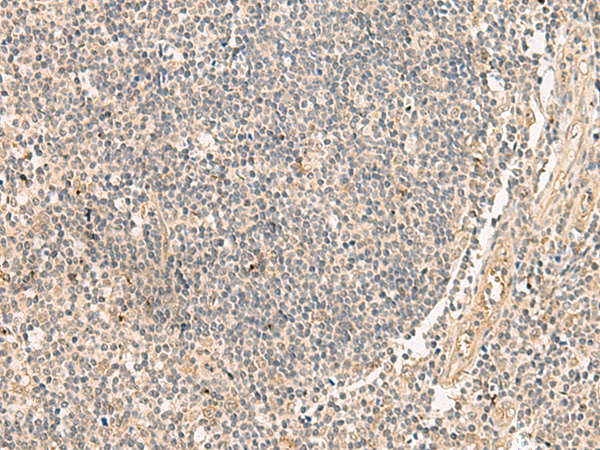

分类: 科研抗体货号: P09905别名: EIF-2B; EIF2Bgamma应用: IHC反应种属: Human, Rat